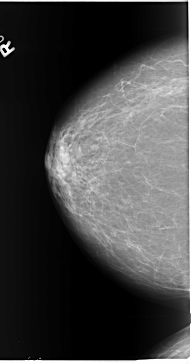

B_3089_1.LEFT_CC

LEFT_CC LINES 5904 PIXELS_PER_LINE 3200 BITS_PER_PIXEL 12 RESOLUTION 50 OVERLAY